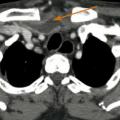

Carcinome épidermoïde du sinus piriforme gauche

CANCER DES VOIES AERODIGESTIVES

CARCINOME EPIDERMOIDE DU SINUS PIRIFORME